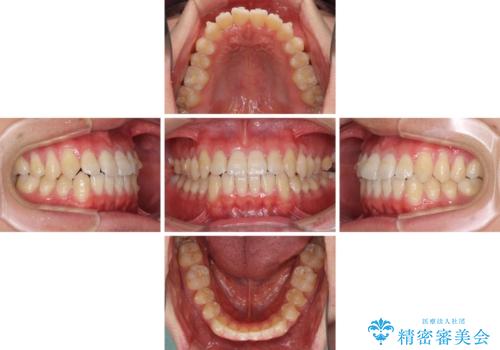

- 上下前歯のデコボコを気にして来院された患者様です。

叢生は軽微であり、費用を抑えて期間もあまりかけずに治療をしたいとのことで、インビザライン・ライトを用いて矯正治療を行うこととしました。

途中通院できなくなり、マウスピースの装着もしっかりとできなかったため、治療期間が長くかかってしまいました。